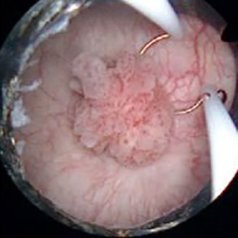

devamı için tıklayınız.Trans-Üretral Rezeksiyon-Mesane (TUR-M): Mesane tümörü patolojik tanı ve tedavisinde ilk ve en sık uygulanan yöntemdir.